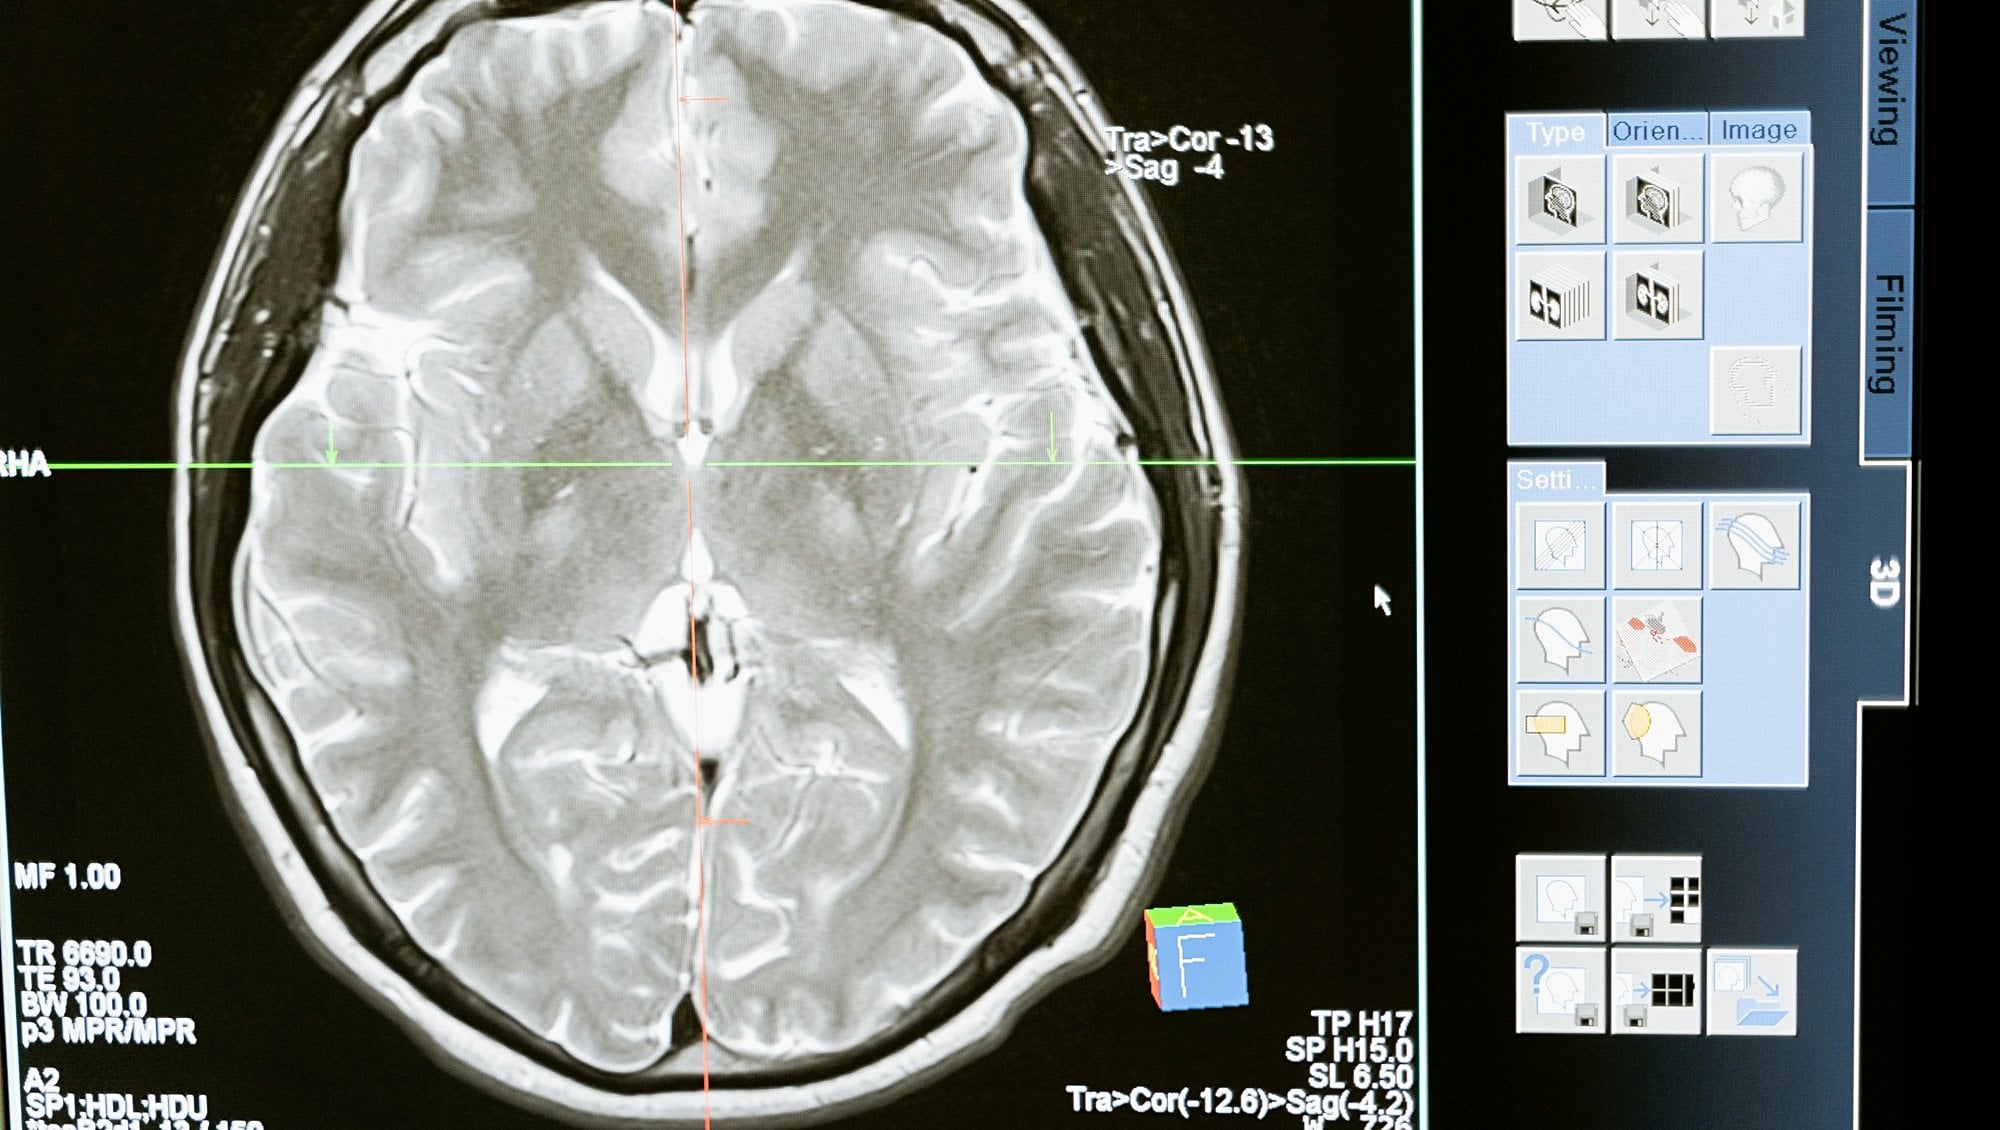

Fosfenler genellikle gözlerin kapalı olduğu, karanlık bir ortamda daha belirgin hale gelir. Ancak fosfenlerin oluşum mekanizması basitçe açıklanabilir: Beynimizdeki sinir hücreleri (nöronlar), elektriksel sinyallerle iletişim kurar. Bu sinyallerin bazıları görme merkezi gibi duyusal alanlarda oluştuğunda, gözden gelen bir uyarı olmasa bile görsel bir algı yaratabilir.

3. Elektriksel Uyarı: Beyin araştırmalarında yapılan deneylerde, görme korteksine elektrik akımı uygulandığında fosfenler oluşabilir. Bu, beynin görme bölgesindeki elektriksel sinyallerin doğrudan görsel bir his yaratabileceğini kanıtlar.

Fosfenler, beyin ve görme sistemi arasındaki bağlantıyı daha iyi anlamamıza olanak tanır. Örneğin, elektriksel uyarılar ile görsel algı yaratabilme fikri, beyin-bilgisayar arayüzü çalışmalarında kullanılıyor. Fosfenler üzerinde yapılan araştırmalar sayesinde, görme engelli bireylerin çevrelerini algılamalarını sağlamak için beyne doğrudan elektriksel sinyaller gönderme potansiyeli araştırılıyor.

Fosfenler ve Beyin-Bilgisayar Arayüzleri

Beyin-bilgisayar arayüzleri (BBAr), fosfenlerin önemini gösteren bir diğer ilginç alandır. Araştırmacılar, beyne gönderilen elektrik sinyalleri ile görme alanında ışık benzeri hislerin oluşturulabileceğini buldular. Bu, gelecekte görme yetisini kaybetmiş bireyler için bir umut ışığı olabilir. Beynin görme bölgesine elektrotlarla bağlanarak elektriksel uyarı verildiğinde, kişi çevresindeki objeleri algılayabilir hale gelebilir.